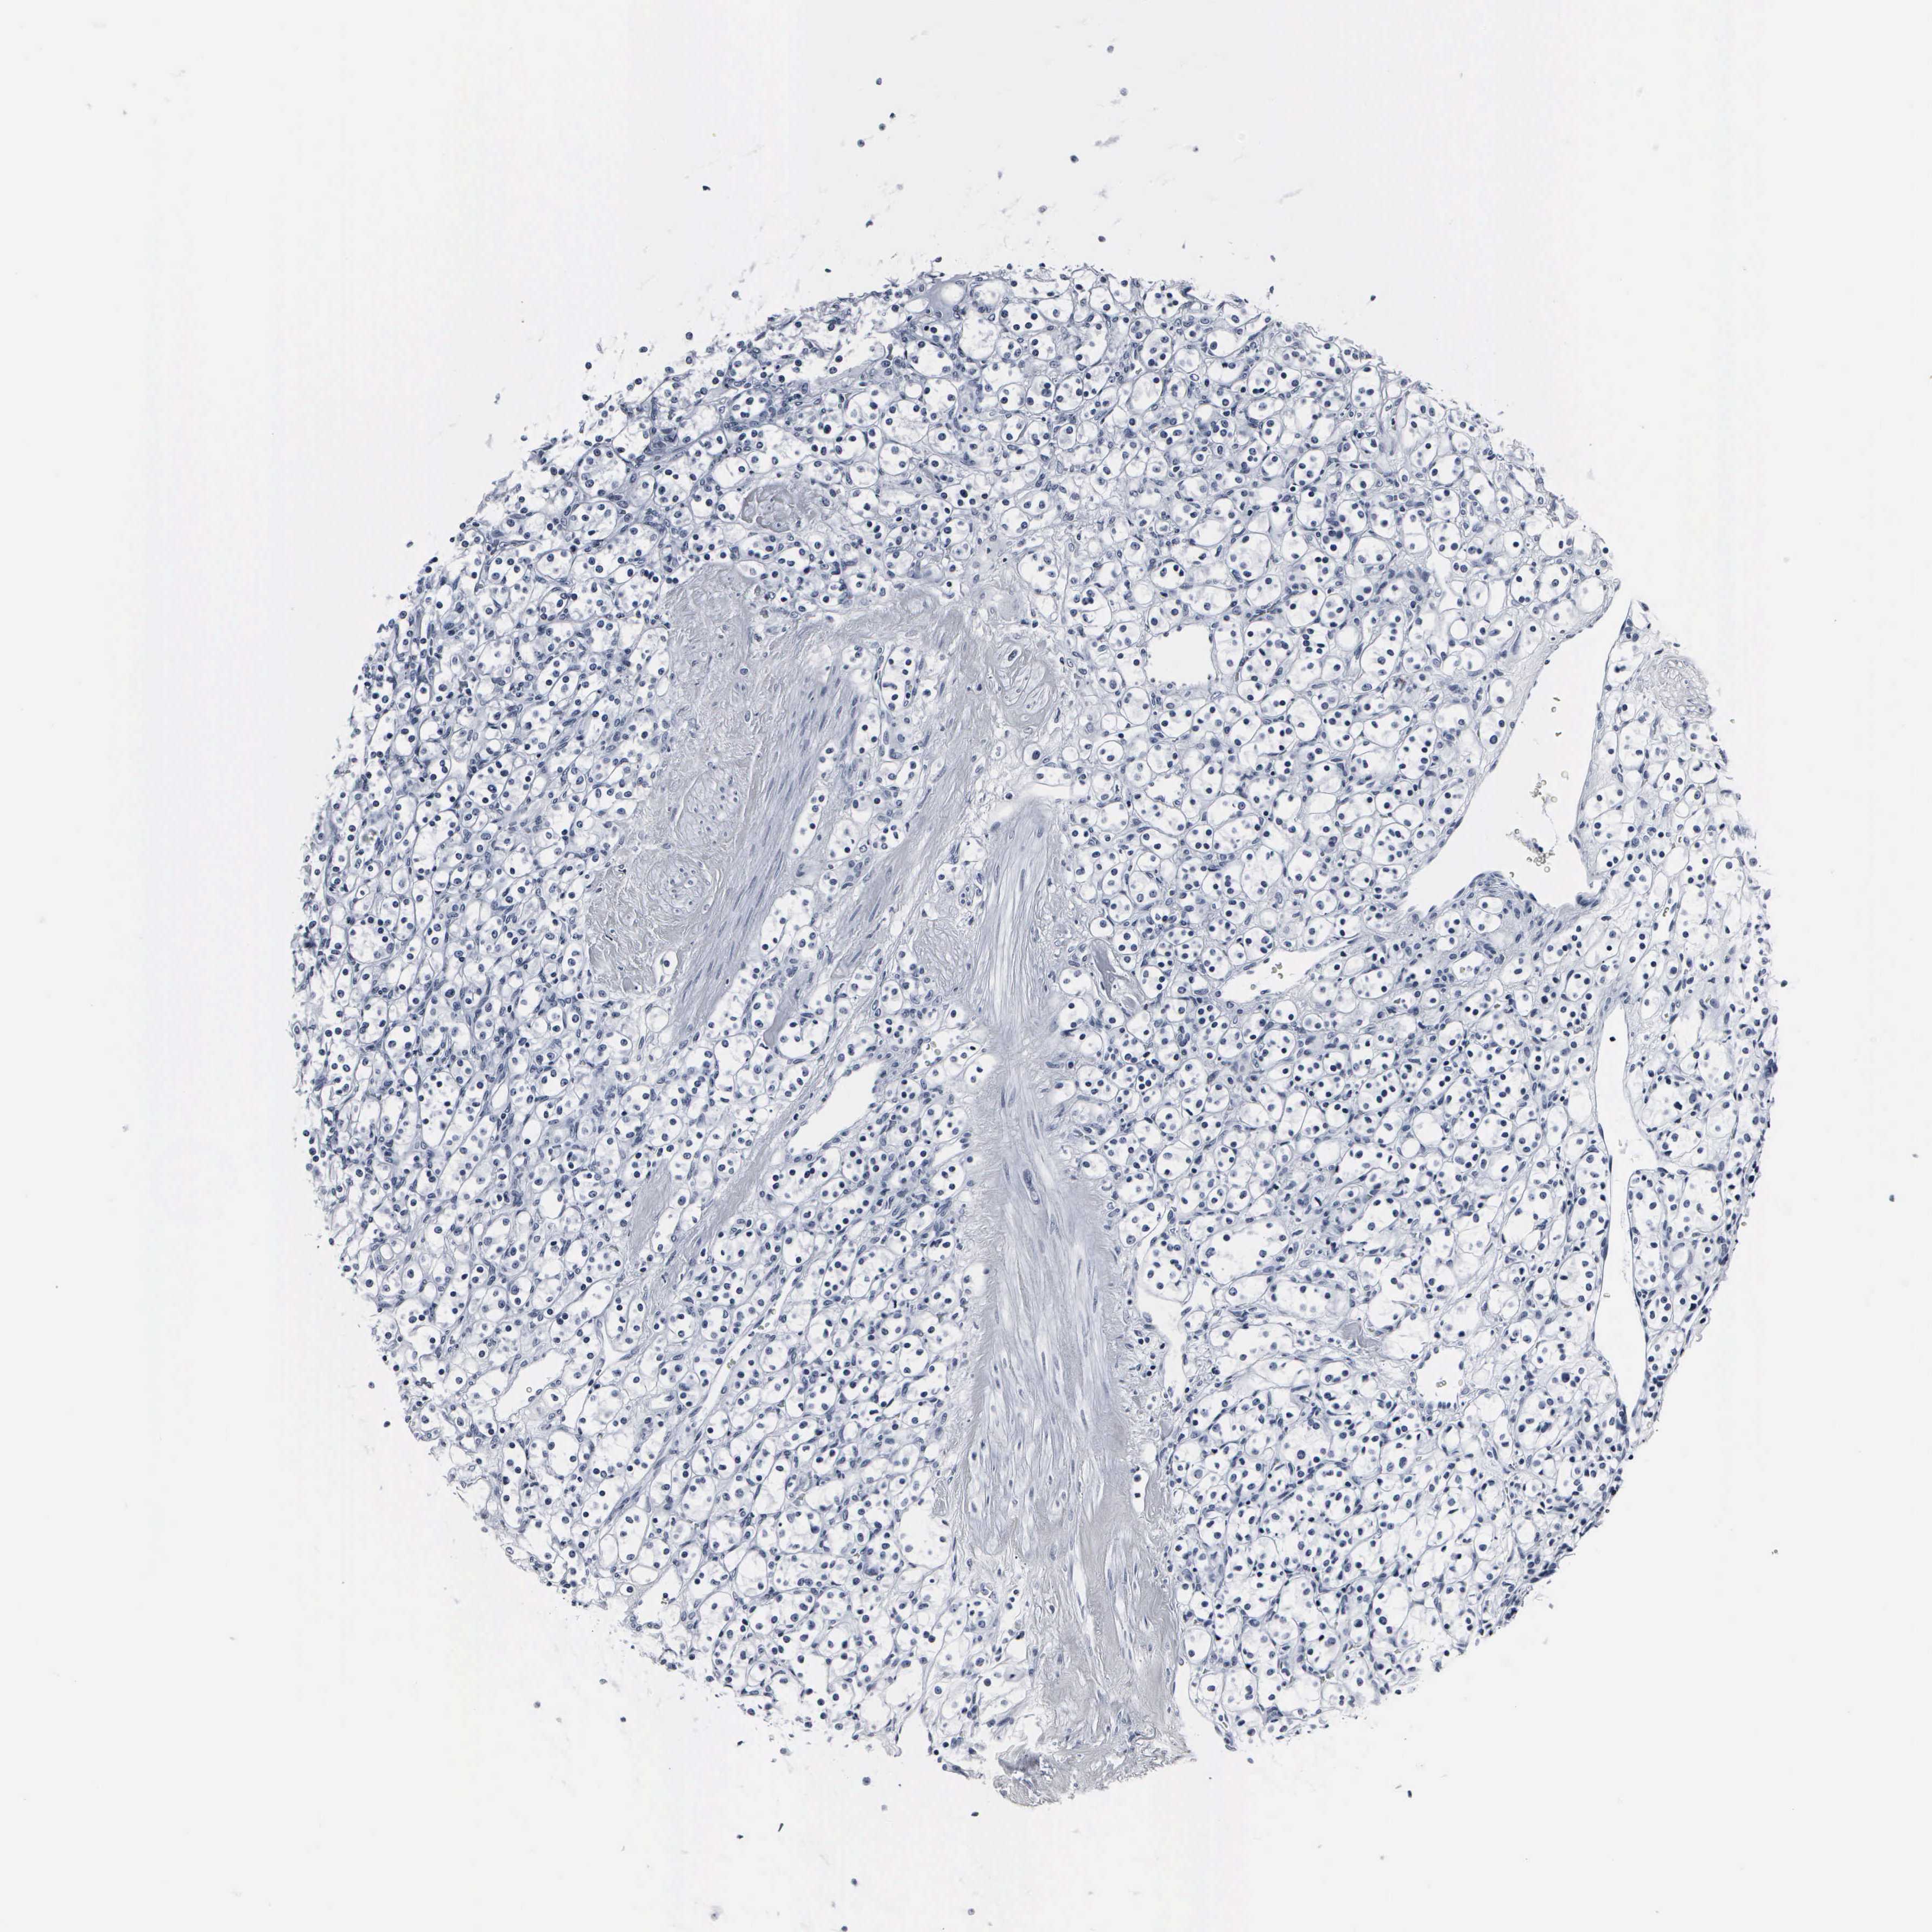

KIDNEY RENAL CLEAR CELL CARCINOMA (VALIDATION) - Interactive survival scatter ploti

The Survival Scatter plot shows the clinical status (i.e. dead or alive) for all individuals in the patient cohort, based on the same data that underlies the corresponding Kaplan-Meier plots. Patients that are alive at last time for follow-up are shown in blue and patients who have died during the study are shown in red.

The x-axis shows the expression levels (FPKM) of the investigated gene in the tumor tissue at the time of diagnosis. The y-axis shows the follow-up time after diagnosis (years). Both axes are complimented with kernel density curves demonstrating the data density over the axes. The top density plot shows the expression levels (FPKM) distribution among dead (red) and alive patients (blue). The right density plot shows the data density of the survived years of dead patients with high and low expression levels respectively, stratified using the cutoff indicated by the vertical dashed line through the Survival Scatter plot. This cutoff is automatically defined based on the FPKM cutoff that minimizes the p-score. The cutoff can be changed by dragging the vertical line or by entering a cutoff value in the square labeled "Current cut-off".

Under the Survival Scatter plot the p-score landscape (black curve; left axis) is shown together with dead median separation (red curve; right axis). Dead median separation is the difference in median mRNA expression between patients who have died with high and low expression, respectively. It is calculated as follows: median FPKM expression of dead patients with high expression - median FPKM expression of dead patients with low expression. This is intended to aid the user in visually exploring custom cutoffs and the associated p-scores and dead median separation.

Individual patient data is displayed and can be filtered by clicking on one or more of the category buttons on the top of the page. Categories describing expression level and patient information include: high, low, alive, dead, female, male and tumor stages. The scale of the x-axis can be toggled between linear and log-scale by clicking on the "x log" button. Mouse-over function shows TCGA ID, patient information and mRNA expression (FPKM) for each patient.

& Survival analysisi

Kaplan-Meier plots summarize results from analysis of correlation between mRNA expression level and patient survival. Patients were divided based on level of expression into one of the two groups "low" (under cut off) or "high" (over cut off). X-axis shows time for survival (years) and y-axis shows the probability of survival, where 1.0 corresponds to 100 percent.

DGCR2 is not prognostic in Kidney Renal Clear Cell Carcinoma (validation)

: 37.05

Average pTPM 48.5

Number of samples 100